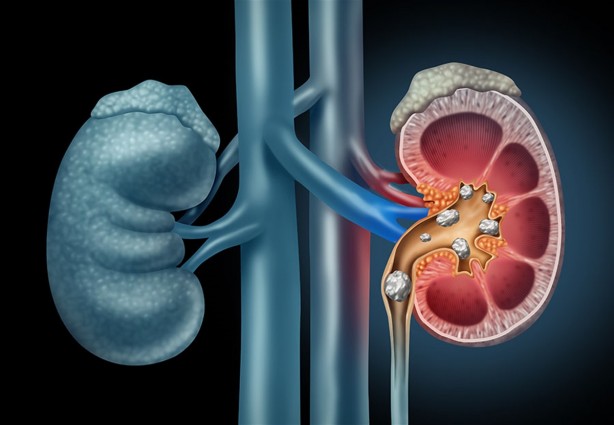

Böbrek taşı oluşumuna yatkın olanlar ayrıca oksalat içeren gıdaların (örneğin pancar, ıspanak ve kakaoda bulunur) ve ürik asit taşları durumunda pürin içeren gıdaların (örneğin hamsi, sardalya, kuşkonmaz vb.) sınırlandırılması gerekir. İşte böbrek sağlığını korumada etkili olduğu tespit edilen yaygın olarak kullanılan 10 besin.